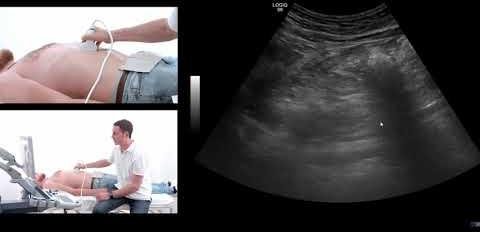

Transabdominal Ultrasound Shows Promise in Monitoring Pancreatic Lesions

Transabdominal ultrasound is a valuable tool for monitoring cystic pancreatic…